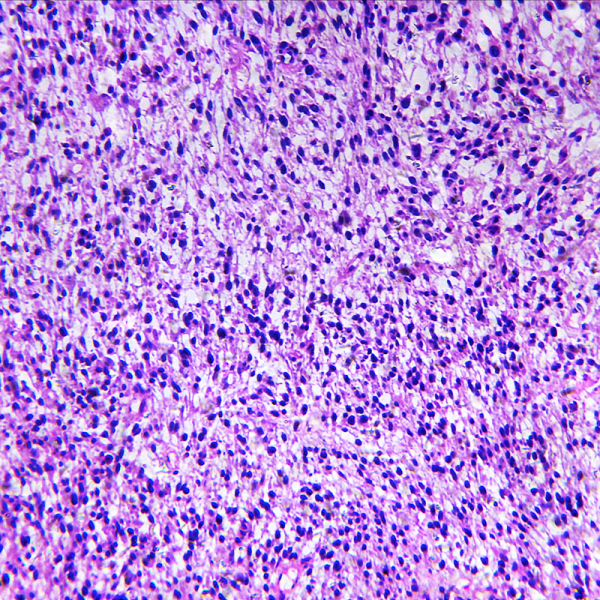

Kā attīstās vēža šūnas?